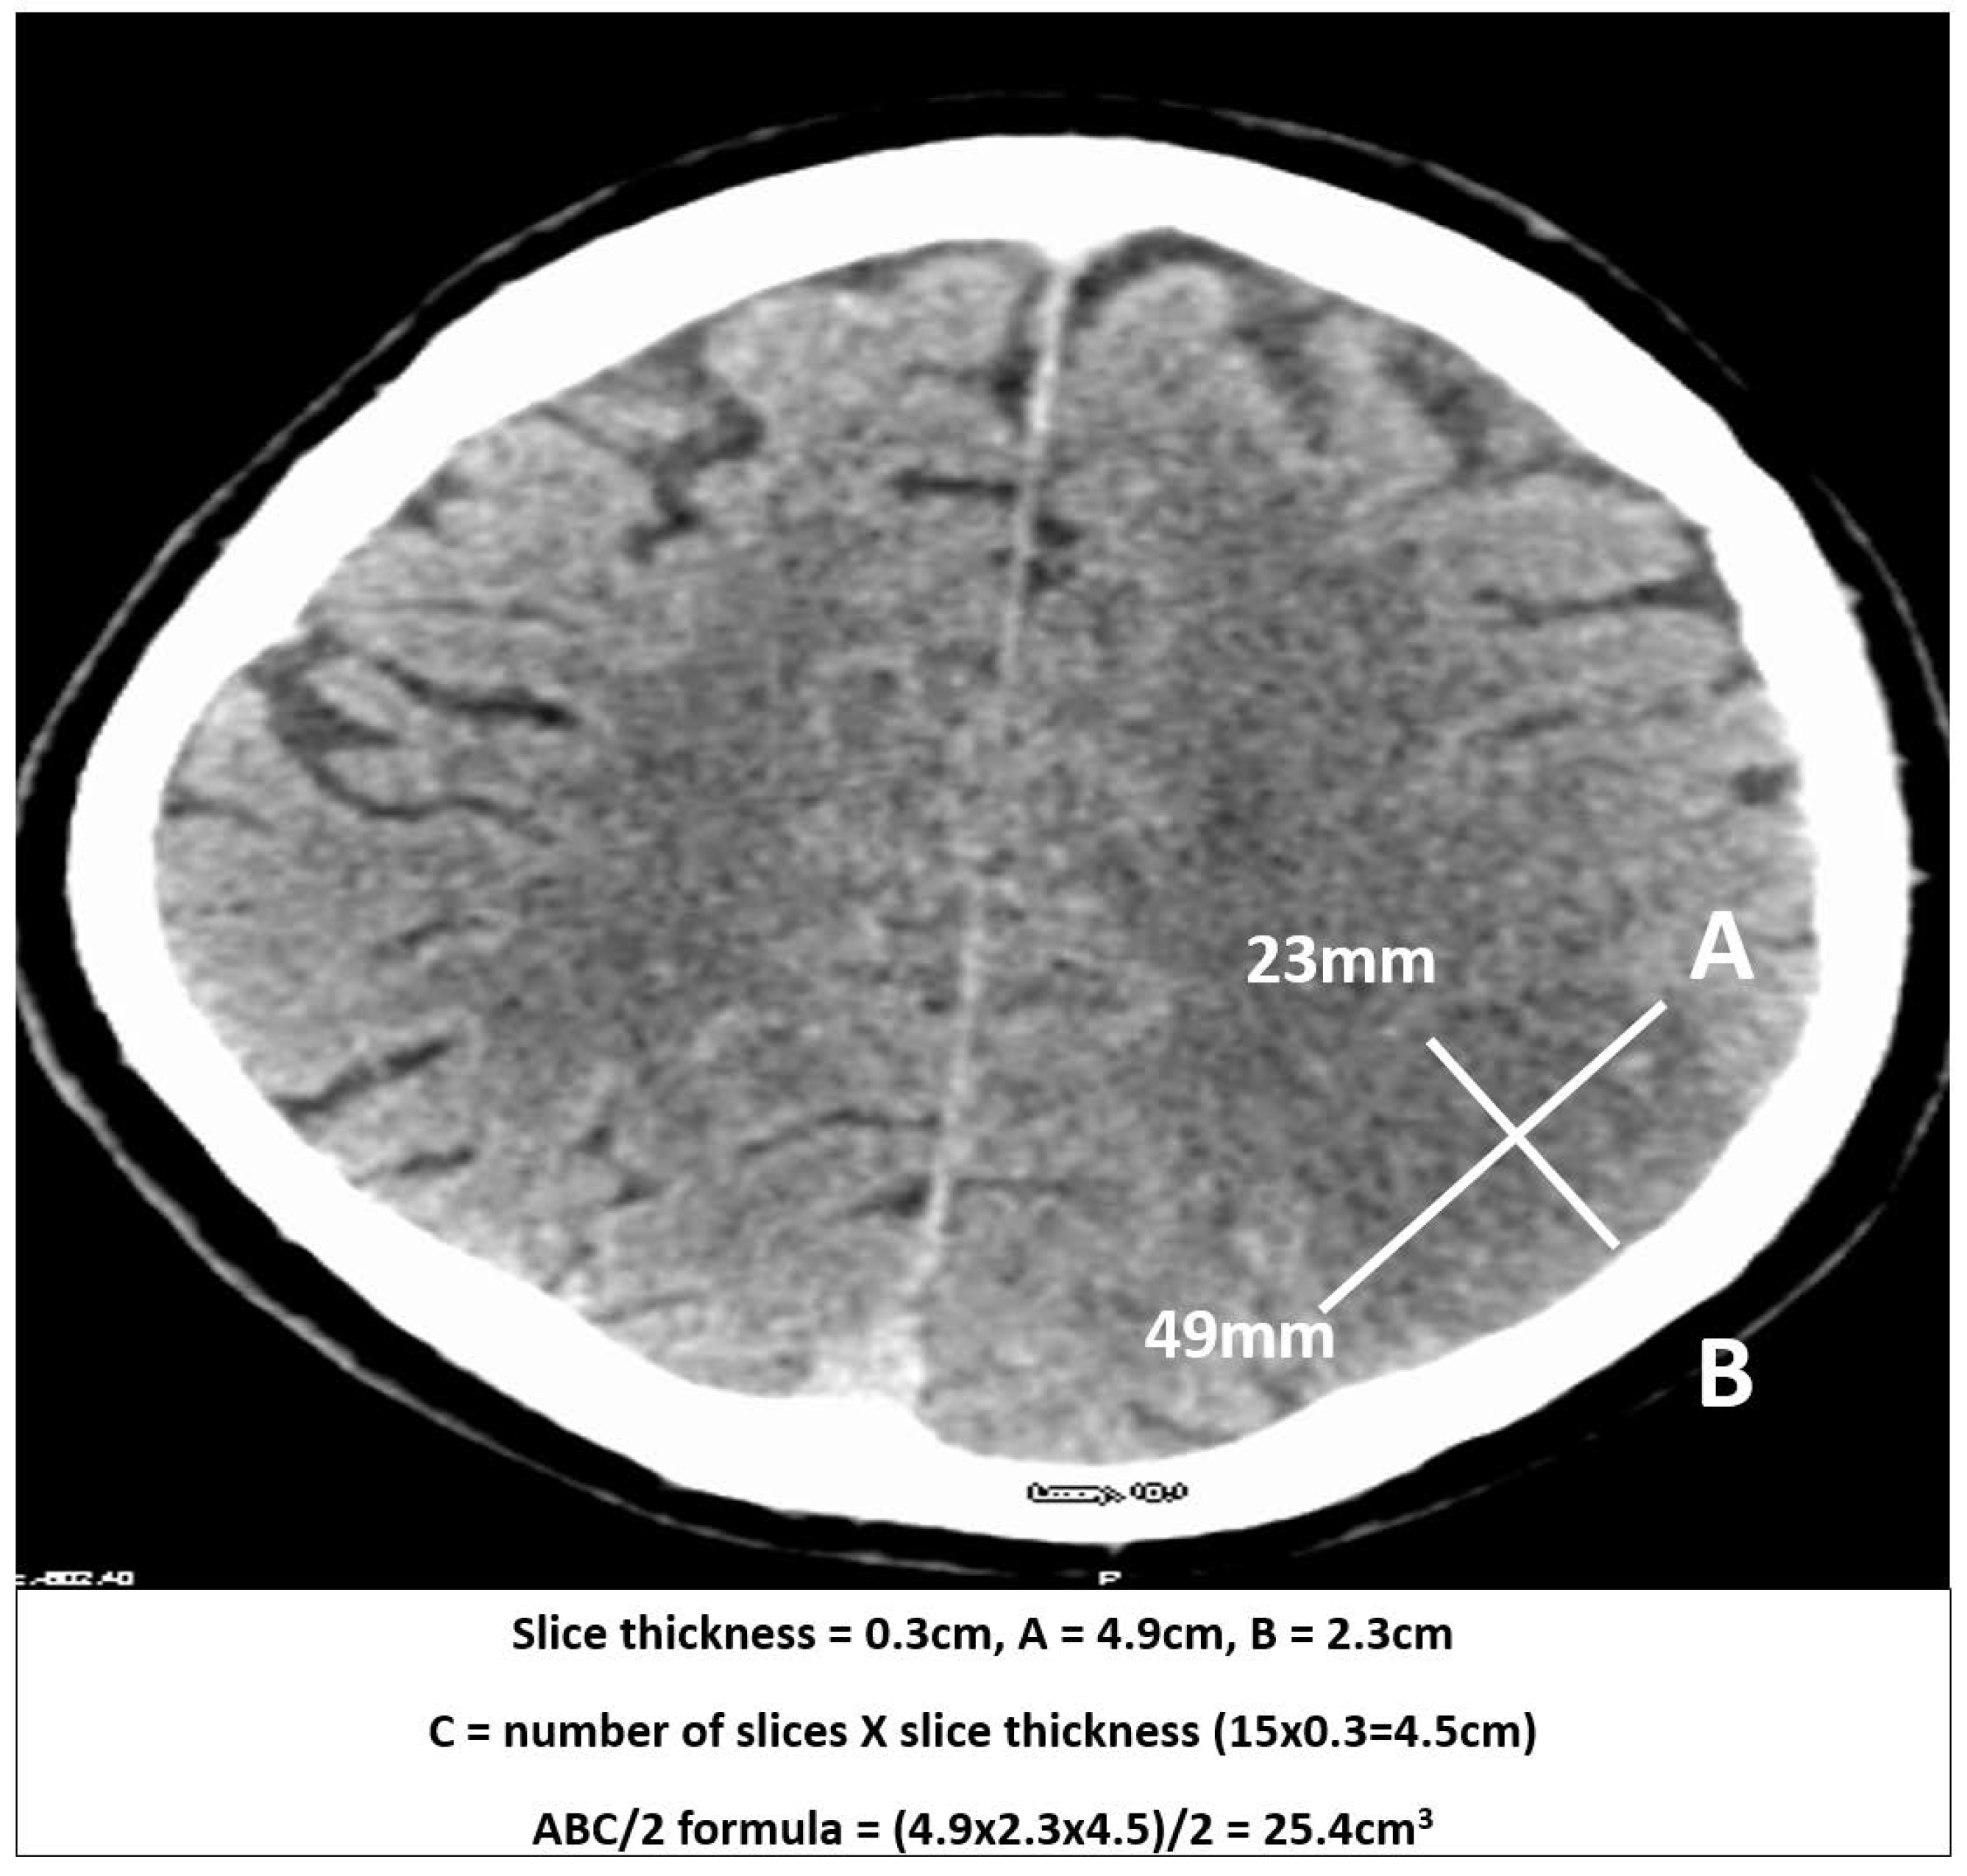

2.2. Measurements